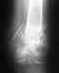

Просто у меня тоже открытый перелом нижней трети левой голени. Сейчас прошло 2 месяца после операции (остеосинтез б/берцовой кости штифтом). По снимкам мой врач говорит, что вокруг перелома образовывается костная мозоль, но хорошо еще видна трещина. И категорически советует вообще не давать нагрузку на ногу еще в течении месяца... А может все-таки можно ногу нагружать?

Надо посмотреть на снимок. Если нагрузку советуют ограничить, для этого возможно множество причин в Вашем случае, которых не было в обсуждавшемся. Может, получилась не очень стабильная фиксация, или запирающие винты небольшого диаметра, или их мало, или линии перелома проникают в сустав, или мало ли почему еще.